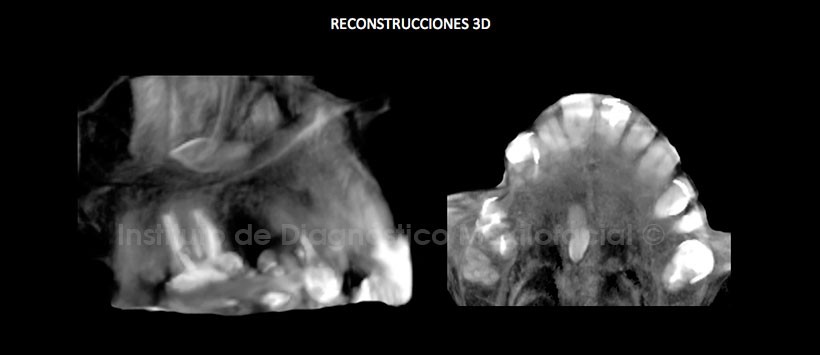

En las reconstrucciones 3D se observa claramente a la pieza 1.3 retenida en el paladar duro y su relación con las estructuras adycantes. (Figura 6)